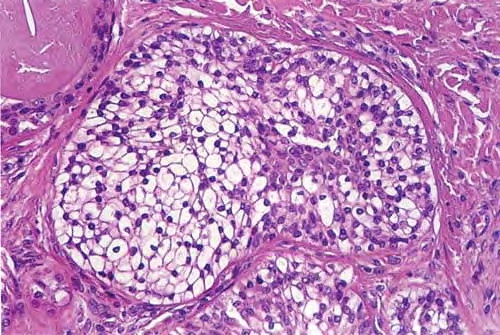

Nodular hidradenoma =الغدوم العرقي العقيدي